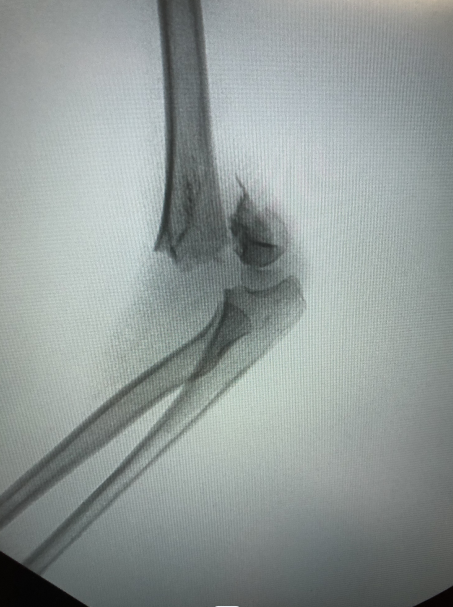

▲肱骨髁上骨折X线平片

小儿骨科康映泉副主任医师接诊后确诊是“肱骨髁上骨折”,骨折完全移位,所幸没有血管神经损伤,但仍需要手术治疗。康映泉副主任医师应用最新治疗手段,即超声引导骨折复位技术,大大降低术中辐射暴露,成功为小晨施行骨折闭合复位内固定术,术中没有伤口,针尾留置皮肤外面,待1个月后骨折愈合即可门诊拔除,无需住院或麻醉,看着无大碍的孩子,小晨爸爸悬着的心终于放下。